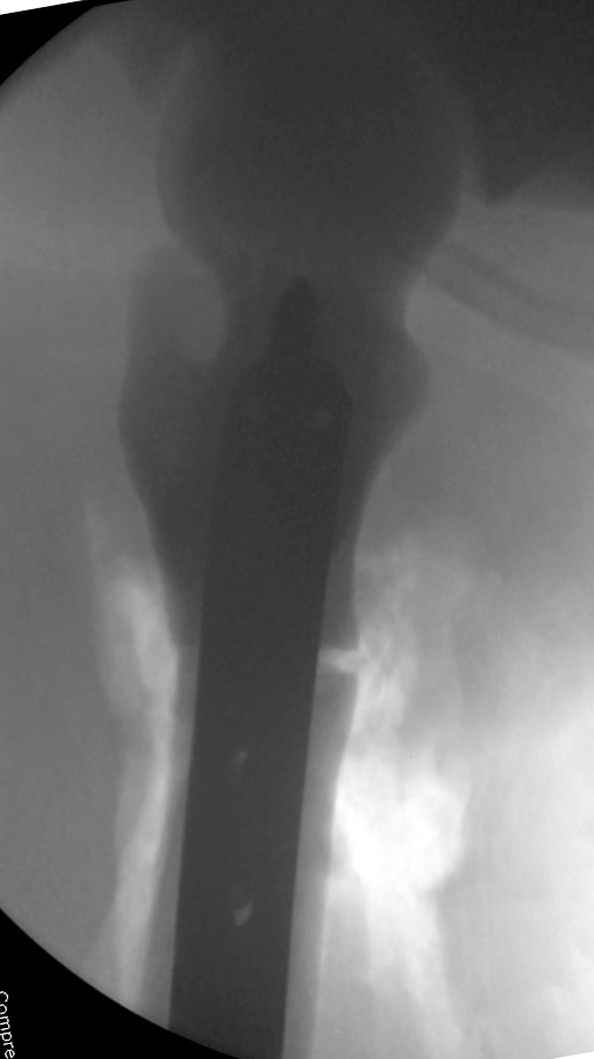

Здесь у меня дополнительные снимки с большим разрешением и в разных режимах, а то те дигитал снимки совсем очень блеклые, может, эти изображени изменят выбор тактики

После неудачной попытки скелетного вытяжения в первом мед.учреждении, после осмотра снимков и изучения истории, поставили диагноз “Остеопетроз” или мраморная болезнь, редкая наследственная костная паталогия, где имеется нарушение формации остеокластов.

Конечно, было бы идеальным применение интрамедуллярного остеосинтеза, но учитывая прежний собственный опыт (лечил перелом бедра) и

публикации, предупреждающие о трудностях при обработке кости (иногда из-за неподготовленности инструментария результатом была неадекватная фиксация перелома, или перенос операции из-за фактора усталости оперирующего персонала), решили применить пластину (и в этом же случае был выбран Synthes plate, так что представитель за два дня

зароботал... на десерт тоже).

Заказаны были дополнительные различные дрели, и на следующий день, усиленной бригадой, больного прооперировали, потратив на каждое отверстие около 25-35 минут, хотя сверлили с охлаждением по нарастающей по диаметру сверл и с их заменой каждые 2 мм сверления.

Теперь стоит задача со сращением перелома, из-за отсутствия литературных данных по применению костных стимуляторов при остеопетрозе, и не зная как поведет в этой среде Grafton, все таки надеюсь, что даст толчок к стимуляцию, решил применить пастообразную деминерализованную костную матрицу, расположив спереди между отломками.